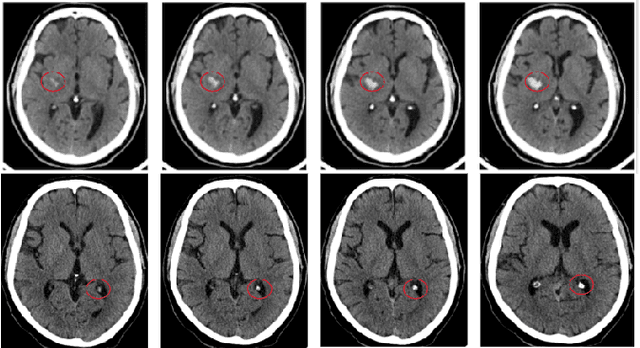

Abstract:Head CT is one of the most commonly performed imaging studied in the Emergency Department setting and Intracranial hemorrhage (ICH) is among the most critical and timesensitive findings to be detected on Head CT. We present BloodNet, a deep learning architecture designed for optimal triaging of Head CTs, with the goal of decreasing the time from CT acquisition to accurate ICH detection. The BloodNet architecture incorporates dependency between the otherwise independent tasks of segmentation and classification, achieving improved classification results. AUCs of 0.9493 and 0.9566 are reported on held out positive-enriched and randomly sampled sets comprised of over 1400 studies acquired from over 10 different hospitals. These results are comparable to previously reported results with smaller number of tagged studies.